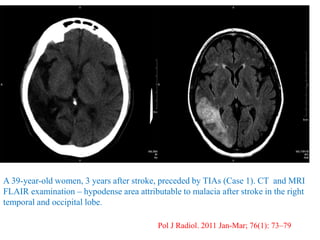

A 39-year-old women, 3 years after stroke, preceded by TIAs (Case 1). CT and MRI

FLAIR examination – hypodense area attributable to malacia after stroke in the right

temporal and occipital lobe.

Pol J Radiol. 2011 Jan-Mar; 76(1): 73–79